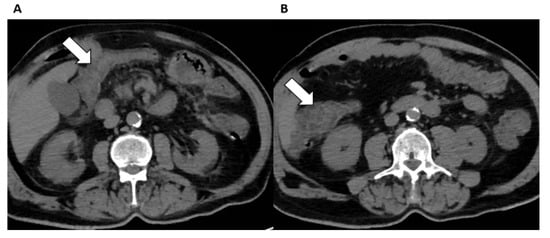

5. Abdominal Organs Involvement

6. Genitourinary Involvement

Kidneys